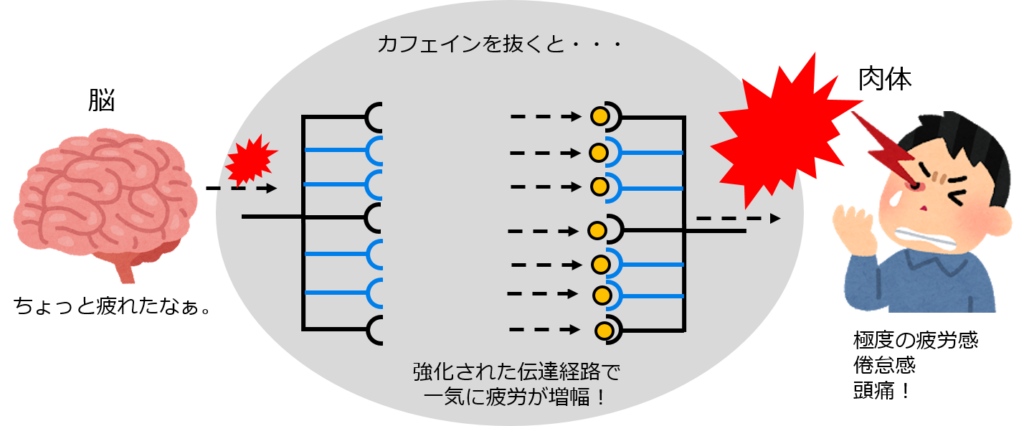

身近な依存症 慢性カフェイン中毒

身近な依存症 慢性カフェイン中毒

身近な依存症 慢性カフェイン中毒